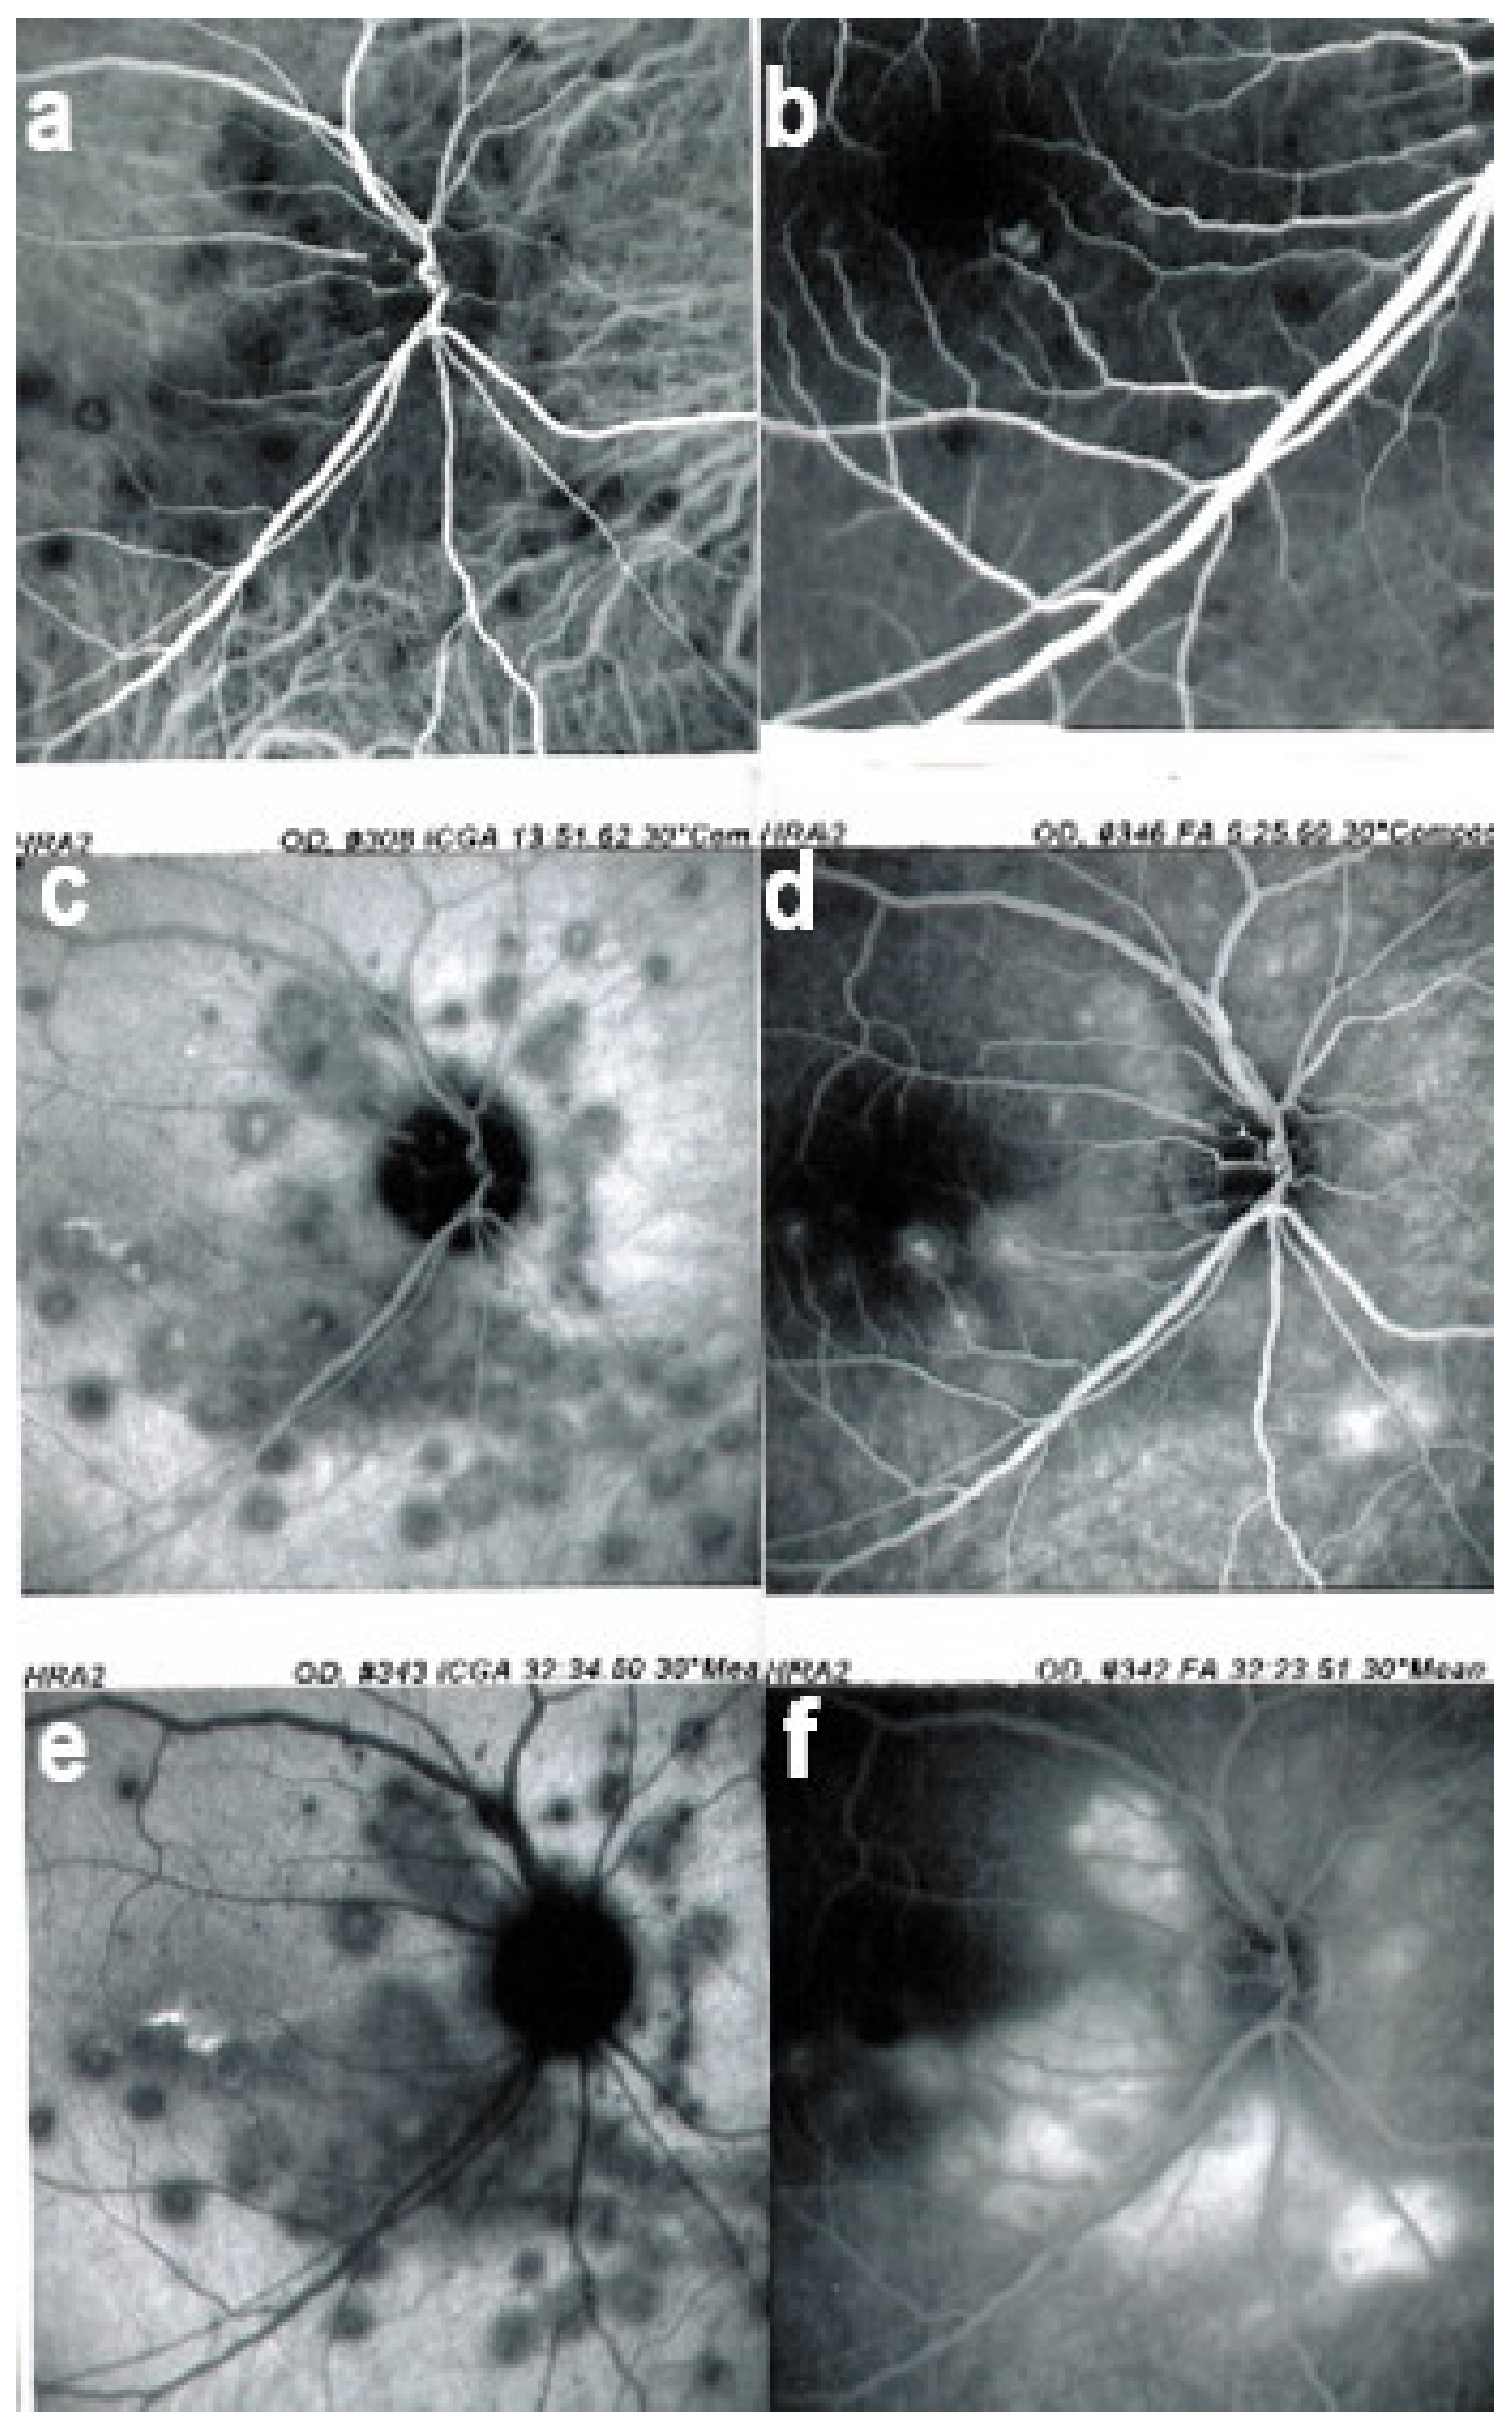

Two main patterns of ICGA signs in choroiditis have been identified, as shown on Figure 3.

(1) Inflammatory choriocapillaris non-perfusion or hypoperfusion, represented on the Figure 3A appears as irregular geographic areas of hypofluorescence or absence of fluorescence (Figure 4). This pattern is found in primary or secondary choriocapillaritis or inflammatory choriocapillaropathies.

(2) On the other hand, stromal choroiditis produces type 2 ICGA pattern characterised by round, often numerous and evenly distributed hypofluorescent dark dots (HDDs) (Figure 5) generated by stromal inflammatory foci that impair the diffusion of the ICG-protein complex, as shown in Figure 3B. If the foci do not occupy the full-thickness of the choroid, they can fade and become isofluorescent in late angiographic frames. Apart from HDDs, ICGA shows additional leakage from larger choroidal vessels that are less distinct and appear fuzzy. (Figure 6). The whole set of angiographic signs that can be identified in stromal choroiditis is listed on Table 1. A grading of these signs allowed to establish a precise quantitative angiographic score [17].